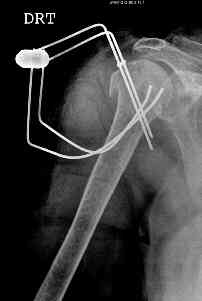

This fx need to be manipulated, reduced and fixed. We developed a minimally invasive ex fix with Ilizarov parts to fix it, we call it “Spider”, which can hold 4 fragments.

Attaching a case.

Best regards,

Nuno Craveiro Lopes

What is your postoperative protocol for the Spider?

How well do patients move their arms with the Spider in place?